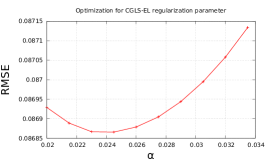

For a fair comparison of different regularizing penalties we initially optimized the regularization parameters (see Fig. 2) with respect to the value of root-mean-square-error (RMSE), defined as:

We found empirically that for EL penalty (20) gives good results for the presented experiments, therefore we will keep it fixed for the rest of our tests. With fixed optimal regularization parameters (see Fig. 2) we perform outer (fixed point) iterations and 5 inner iterations of algorithm 1 with different penalties (see Fig. 3).